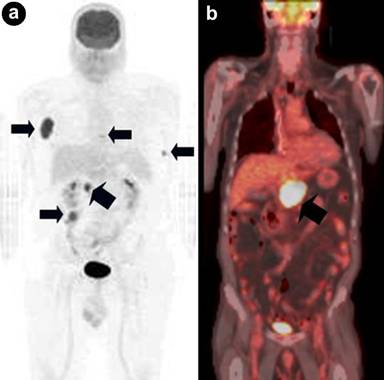

Lymphoma consists of Hodgkin lymphoma (15%) and non-Hodgkin lymphoma (85%). Together, they account for less than 10% of all cancers. Non-Hodgkin lymphoma is more aggressive than Hodgkin lymphoma, having a tendency for extra-nodal involvement. Non-Hodgkin lymphoma makes up of two subtypes: low-grade or aggressive non-Hodgkin lymphoma. Only Hodgkin lymphoma and aggressive non-Hodgkin lymphoma show a high affinity for FDG. An autopsy study showed that up to 30% of non-Hodgkin lymphomas metastasize to the pancreas [11]. Approximately 70% of pancreatic lymphomas respond well to chemotherapy [11]. Current evidence indicates that PET/CT is extremely useful in the staging and restaging of FDG-avid lymphomas (Figure 12). In addition, PET has a prognostic value in lymphoma treatment.

|

Figure 12. a. Fused axial PET/CT image shows a hypermetabolic lesion of non-Hodgkin lymphoma of the pancreas (arrow). The other two bright “spots? represent normal kidney excretion of FDG tracer. b. Corresponding axial CT image (arrow). |

f) Pancreatic Metastasis from Melanoma

Melanoma is the sixth most common cancer in the United States. The incidence has tripled in the white population in the last 20 years. The most common metastatic sites are lungs, lymph nodes, gastrointestinal tract, brain, and bone (Figure 14). Pancreatic metastases occur in less than 5% of patients with distant metastatic sites (Figure 14). Current evidence supports using PET/CT in staging, restaging, and monitoring therapy for stage III and IV because of superior accuracy of PET/CT compared to CT alone in detecting distant metastases [13]. Early detection of metastases is crucial for patients with stage IV melanoma because, in selected cases, metastasectomy can improve the 5-year survival rate (20 months vs. 8 months).

Figure 14. a. Coronal PET maximum intensity projection image shows metastases of melanoma to the head of the pancreas (large arrow), right axilla, lower thoracic spine, right mesentery and left rib (small arrows). b. Coronal fused PET/CT image of another patient with melanoma metastasizing to the pancreas (arrow). |

COEXISTING CANCERS

Coexisting cancers may be encountered in high risk patients due to multiples factors, such as long duration exposure to carcinogens impacting numerous organ systems, mutational genetic predisposition, and immunocompromised/immunodepressed status. As mentioned above, PET/CT, with whole body assessment, provides a more comprehensive evaluation than other cross-sectional imaging modalities and may detect unanticipated hypermetabolic pathologic processes (Figure 15). The exact frequency of PET/CT incidental detection of additional primary malignancies during evaluation of unrelated cancer is not well known. The reported rate of such findings is about 5% for general oncologic patients [14]. This rate may be higher should clinical, imaging, and histopathological follow-up be more thorough with the involved patient groups. The most frequent malignant PET incidental findings are colorectal, thyroid, and lung lesions. All these unexpectedly detected lesions should be subjected to close clinical scrutiny with good collaboration between the imagers and referring physicians.

Figure 15. a. Coexisting cancers of the lung and pancreas (PET maximum intensity projection image; arrows). b. c. Corresponding fused axial PET/CT images (arrows). |